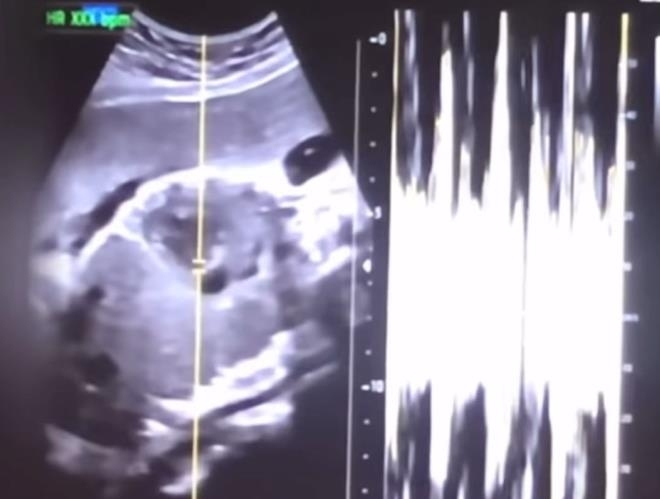

검찰에 따르면 윤씨 등은 지난해 6월 25일 임신 34∼36주 차인 권씨에 대해 제왕절개 수술을 해 태아를 출산하게 한 뒤, 미리 준비한 사각포로 태아를 덮고 냉동고에 넣어 살해한 혐의를 받는다.